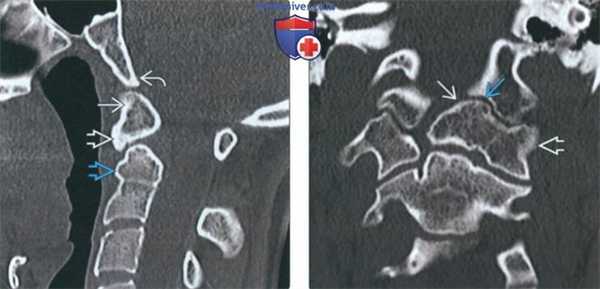

(Слева) На сагиттальной КТ в костном окне определяется слияние дистопической зубовидной кости с передней дугой С1. Вершина ската минимально ремоделирована (уплощена). Определяется дисплазия короткого и округлого зубовидного отростка.

(Справа) На корональной КТ в костном окне определяется эксцентрическое слияние дистопической зубовидной кости с передней дугой и боковой массой С1 слева. Обратите также внимание на патологический псевдосустав между зубовидной костью и левым затылочным мыщелком.